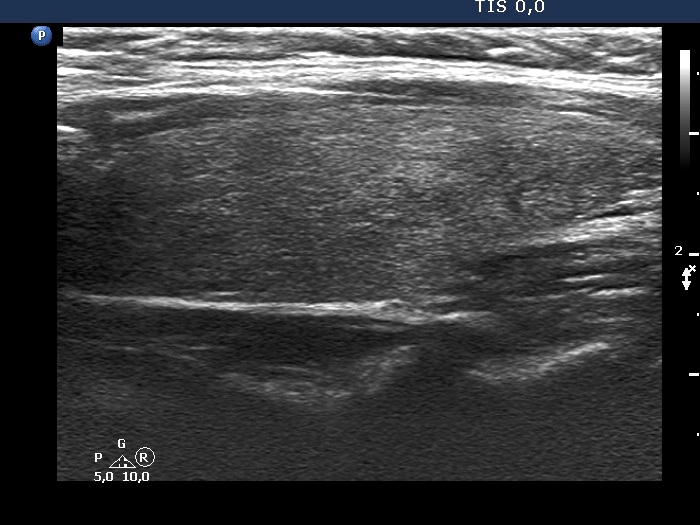

25 months after the first examination (ultrasonographic picture 7)

Left lobe, longitudinal view. There is a discrete, minimally hypoechoic lesion in the lower part of the lobe.